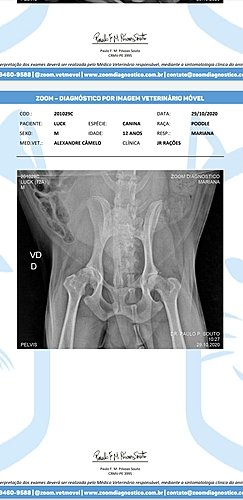

Luck é meu cachorro a 12 anos, até dia 27/10 ele tava andando normal, fomos passear de manhã, mas de tarde ele perdeu a força nas patinhas traseiras, levei ele no veterinário Alexandre dia 28/10 e ele passou 2 medicamentos prediderme 20mg (38,80)e cronidor 12mg 2x ao dia por 20 dias que dá 2 caixas com 10 comprimidos (2x 59.90) e um raio x (200,00), todos esses já comprei e ainda preciso pagar + consulta (70,00). Fora isso, depois que saiu o resultado do raio x alexandre passou o tratamento pra 2 meses com o remédio Gerioox 2 Comprimidos por dia, que dá 4 caixas de 30 comprimidos pra os 2 meses, as 4 caixas são (425,12) + 75,00 (Seniox) + 71,90 (Milgama- esse será pra o resto da vida). A conta total disso fica em 1.001, 00. Dinheiro que foge muito do meu orçamento, me encontro totalmente seNm saber o que fazer e pedindo a vocês qualquer contribuição. É muito doloroso ver ele da forma que está pois ele sente muita dor, não anda devido a isso e tem dificuldade pra defecar porque é uma região proxima que ao fazer força pra defecar doi as articulacoes também e tudo isso tem como melhorar se eu conseguir seguir o tratamento. Preciso muito da ajuda de vocês, eu nem sei como agradecer, quem não puder doar, compartilha, vai ajudar muito. Eu quero muito que meu bichinho fique bem, o Veterinário disse que ele pode voltar a andar e não sentir dor. Muita gratidão a quem ajudar seja de que forma for. Muita gratidão, mesmo.

*** Vou anexar fotos do diagnóstico, dos preços de remédios e etc.